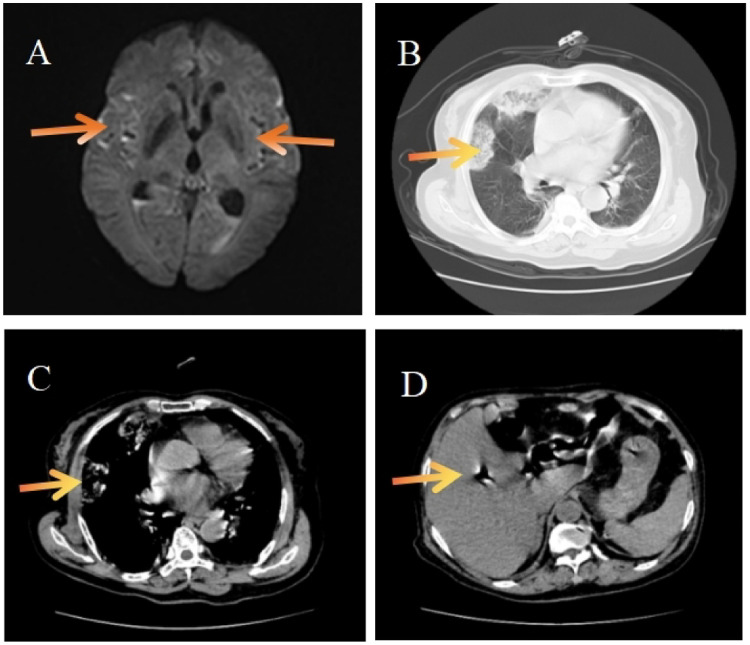

Hypervirulent Klebsiella pneumoniae is a recently identified pathotype characterized by high virulence and rapid dissemination. It is associated with invasive infections at multiple anatomical sites, including liver abscesses, necrotizing fasciitis, meningitis, myositis, and endophthalmitis. It has emerged as a significant threat to public health due to its aggressive clinical course and high mortality rate. This case presents a 63-year-old female diabetic patient who developed lung abscess, liver abscess, and bacterial meningitis. Typical clinical manifestations confirmed through imaging, microbiological culture analysis, and whole-genome sequencing (ST65-K1) revealed Hypervirulent Klebsiella pneumoniae infection. The patient was comatose with purulent cerebrospinal fluid and obstructed drainage. Such severe cases of Hypervirulent Klebsiella pneumoniae intracranial infection are extremely rare. Early cerebrospinal fluid exchange, combined with intrathecal amikacin injection, was initiated. After one month of active treatment, the patient exhibited improved clinical outcomes and was subsequently discharged. This case highlights that patients with diabetes, particularly those presenting with high-risk comorbidities, are predisposed to developing triggering factors for Klebsiella pneumoniae invasive syndrome Klebsiella pneumoniae invasive syndrome. Early identification and implementation of individualized cerebrospinal fluid exchange therapy combined with intrathecal antibiotic therapy in critically ill meningitis patients infected with Klebsiella pneumoniae invasive syndrome are pivotal for improving prognosis. Collectively, these findings provide novel insights and a valuable framework for developing future therapeutically efficacious strategies for the management of Hypervirulent Klebsiella pneumoniae. However, this regimen does not standard-of-care, and further evidence is required to establish its safety and clinical effectiveness.